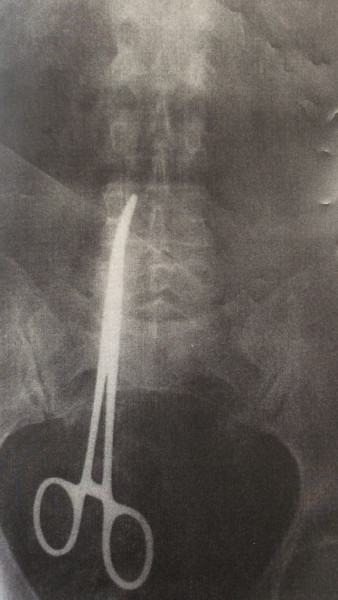

63-летняя жительница Красноярска в апреле 2017 года перенесла операцию по поводу грыжи, после чего постоянно жаловалась на сильные боли в животе.

Истинную причину врачи обнаружили с помощью компьютерной  томографии - у женщины в кишечной полости находился 16-сантиметровый  медицинский  зажим, который забыли медики поле операции. Чтобы его извлечь, пришлось делать еще одну операцию.